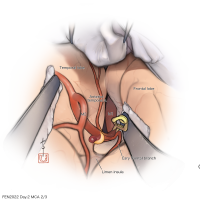

FEN2022シリーズ